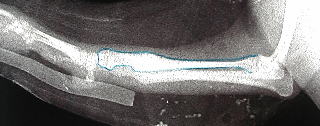

術前の骨折像

橈骨と尺骨が手根骨側で骨折している